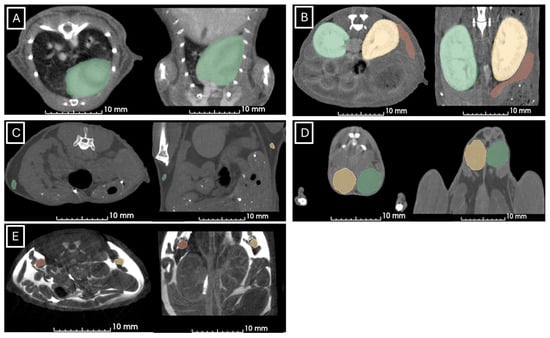

Figure 1 and Figure 2 show examples of ultrasound and microCT diameter measurements. Figure 3 shows examples of manual segmentation.

Figure 1.

Representative images of ultrasound diameter measurements in (A) heart in axial (left) and longitudinal (right) views, (B) spleen in axial (left) and longitudinal (right) views, (C) inguinal lymph nodes in axial (left) and longitudinal (right) views, (D) left kidney in axial (left) and longitudinal (right) views, (E) left testicle in axial (left) and longitudinal (right) views, and (F) left ovary in axial (left) and longitudinal (right) views. In all cases, the diameters are marked with dotted, white, or black lines.